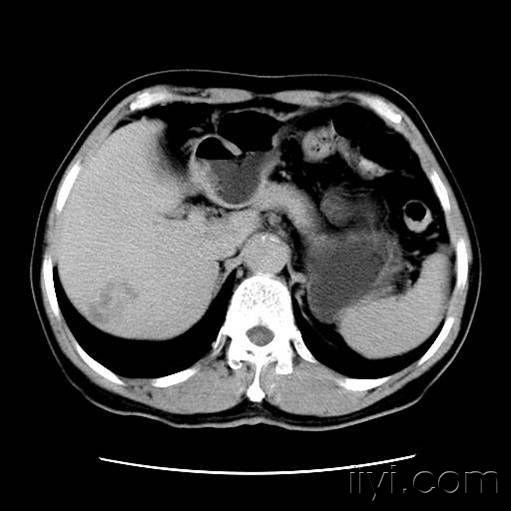

肝脏罕见的良性肿物:炎性假瘤 - 好大夫在线

图片尺寸2954x2537

图片尺寸2831x3093